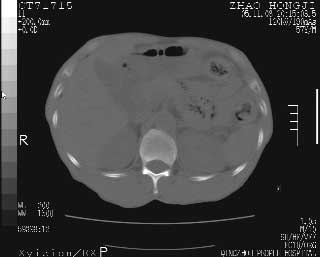

临床资料:男性,57岁,上腹部疼痛并5天,突然加重并延及全腹伴恶心5小时入院。胰淀粉酶化验在正常范围。检查:腹肌紧张,全腹压痛、反跳痛,尤以右上腹部为著。肠鸣音减低。血常规:wbc14.6x10/9, n:11.3x10/9 ,血压:135/90mmhg. 胸部透视:腹部肠腔轻度张气,未见其它异常改变。

肝右前缘少量积气,其他未见明显异常.考虑上消化道穿孔.

小网膜囊积气液,胃壁僵硬。考虑胃穿孔。

小膜网膜积液,肝缘气腹征,上消化道穿孔。

肝缘见少许气体,胰尾部见少许气体包饶(蓝色圈),12指肠上部或球部邻近胆囊周边也可见少许气体影(黄色圈),并忖托出胆囊壁,12指肠远段肠道内未见明显气体(白色箭)。

肝脏前缘见少量积气、胰尾部见少许气体包饶,肾前筋膜未见增厚,临床淀粉酶不高,意见:上消化道穿孔。

消化道穿孔。12指肠球部周和胰周积气考虑12指肠穿孔可能性大。

入院3小时后行剖腹探查术,见腹腔内大量脓性混浊液约1000ml,十二指肠球部溃疡穿孔,溃疡面约2.5x2cm,穿孔直径约0.6cm。胃内容物外益,周围组织炎性水肿明显。行十二指肠穿孔修补术。术后诊断:

1、十二指肠溃疡穿孔

2、弥漫性腹膜炎

对于少量的腹腔游离气体,ct检查较普通透视有绝对的优势,它不仅可以看到肝脏前上缘的气体,而且还能够看到小网膜区的游离气体。从而可以肯定诊断。各位分析战友的很好,感谢大家的参入!